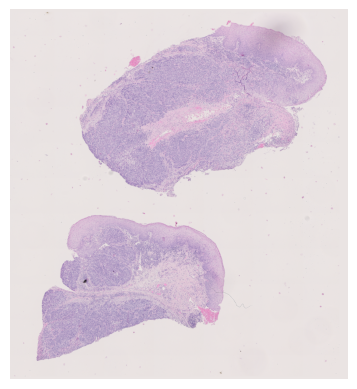

In summary, the data we used includes three key components: (1) the multi-channel, spatial Raman spectra of tissue samples, collected using Raman spectroscopy, (2) the H&E stained images of the corresponding samples, and (3) the tumour annotations (from pathologists) which segment the input. \figurereffig:e341-sample shows these three sources for a sample from the dataset.

fig:e341-sample

\subfigure[Raman channel]

\subfigure[H&E staining]

\subfigure[Annotated staining]